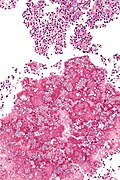

Coccidioidomycosis

General

- Organism: Coccidioides.

- Specific organism: Coccidioides immitis.

- Usu. from soil.

- Typical locations: lung, oral cavity.[12]

- +/-Immunodeficiency.[13]

- Predominantly southwest USA and Mexico.[14]

Microscopic

Features:

- Forms spherules 60-80 μm in size.[9]

- Contain endospores 1-5 μm in diameter.

Notes:

- Spherules may be described as a "bag of marbles".

Images

- Coccidioidomycosis - intermed mag.jpg

Coccidioidomycosis - intermed. mag. (WC)

- Coccidioidomycosis - high mag.jpg

Coccidioidomycosis - high mag. (WC)